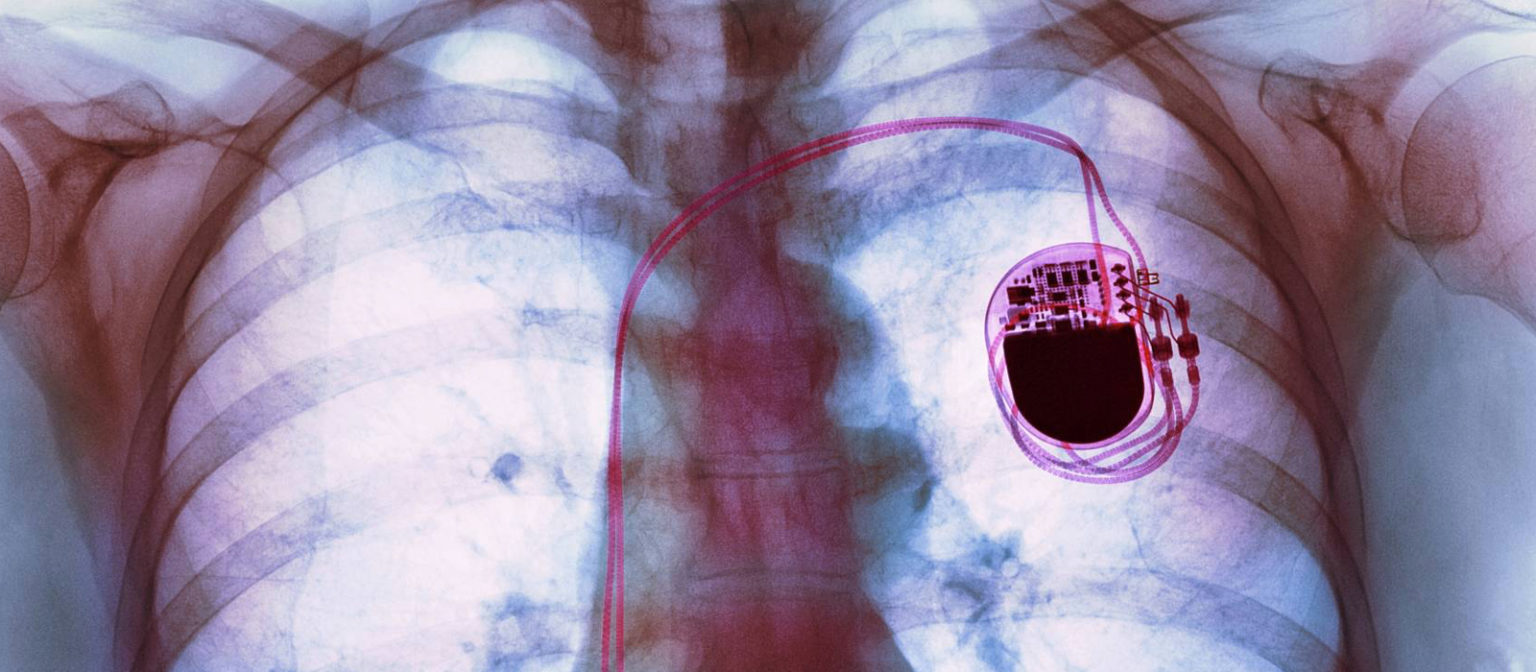

Des appareils aussi courants que les smartphones, tablettes, et même certains accessoires comme les écouteurs et chargeurs sans… Plus de 70 000 pace maker (PM) sont posés en France chaque année (70% après 65 ans) 700 000 personnes vivent avec un (PM ) 80 000 avec un défibrillateur automatique implantable (DAI)

Cependant, de nombreuses personnes se posent la question suivante : "Peut-on mourir avec un pacemaker ?" Dans cet article, nous allons découvrir les risques et les précautions liés à l'utilisation d'un pacemaker. Je n'ai pas été prévenue que j'entendrais et sentirais les vibrations de l'appareil tout comme l'impulsion électrique dans le ventricule gauche. Les champs magnétiques, omniprésents dans notre environnement moderne, peuvent interférer avec ces dispositifs cardiaques

Pose de pacemaker sans sonde une innovation majeure réalisée au CHU de Poitiers Site du CHU. Le cœur finira par s'arrêter, même avec un stimulateur en place. Fin de vie naturelle : Le pacemaker n'empêche pas une mort naturelle

Pacemaker en ICD Deventer Ziekenhuis. Des appareils aussi courants que les smartphones, tablettes, et même certains accessoires comme les écouteurs et chargeurs sans… Pourquoi le pacemaker n'empêche pas de mourir? Le pacemaker n'empêche bien entendu pas de mourir car le coeur s'arrêtera malgré tout de se contracter tôt ou tard.